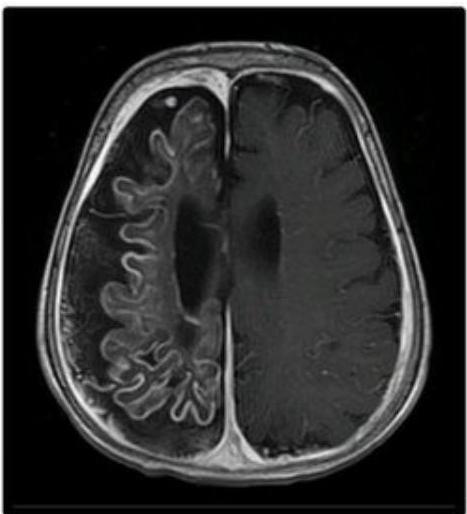

- Best Diagnostic Study: Brain MRI with gadolinium contrast (demonstrates leptomeningeal angioma).

- Brain Atrophy & Calcification: Underlying brain becomes atrophic and calcified (“Tram track” calcification).